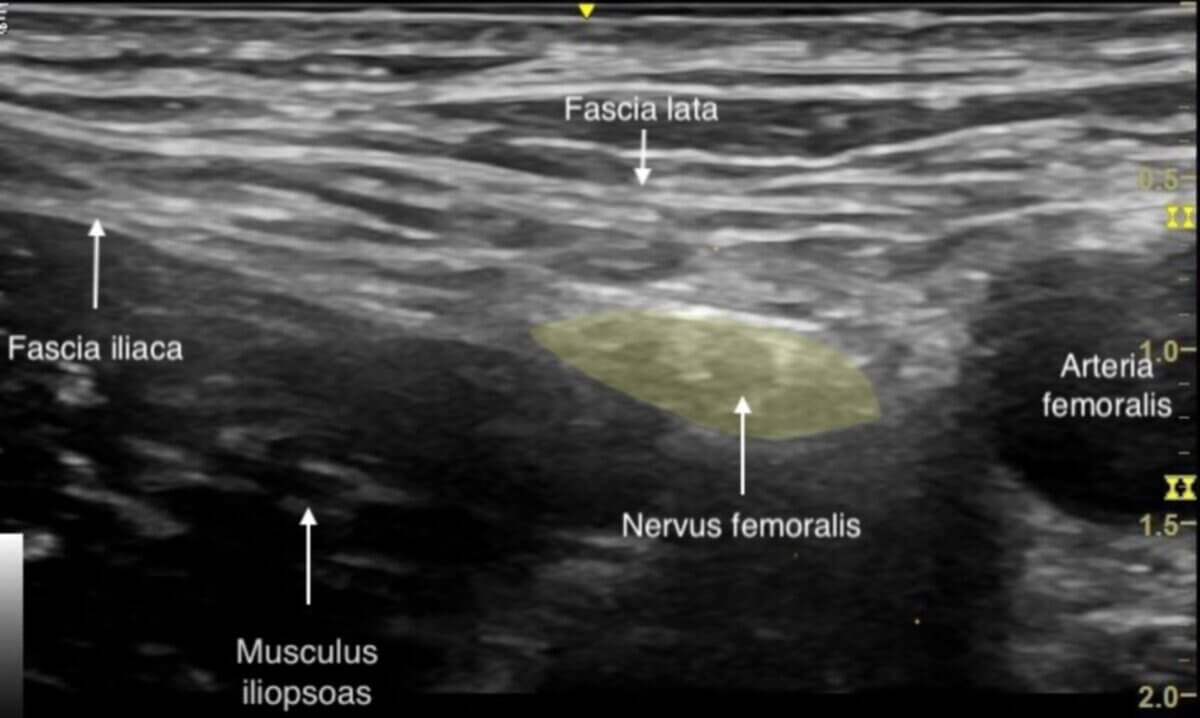

Der Patient befindet sich in Rückenlage. Die Punktion erfolgt heute (2025) in der Regel ultraschallgesteuert, da hierdurch nachweislich eine erhöhte Erfolgsrate erzielt wird. Zudem treten Gefäß- und Nervenverletzungen seltener auf und es ist eine geringere Menge des Lokalanästhetikums nötig. Die Punktion kann in In-Plane- oder Out-of-Plane-Technik erfolgen.

- der Ultraschallkopf wird auf Höhe der Leistenfalte transversal aufgesetzt

- die Femoralgefäße, der Musculus iliopsoas und der Nervus femoralis werden identifiziert

- Punktionsziel ist der laterale Rand des Nervs

- Fascia lata und Fascia iliaca werden durchstochen – hierbei kann es durch die derbe Beschaffenheit der Faszien zu einem plötzlichen Widerstandsverlust kommen.

- die Injektion des Lokalanästhetikums erfolgt zwischen Fascia iliaca und lateraler Nervenbegrenzung (ca. 10 - 20 ml)